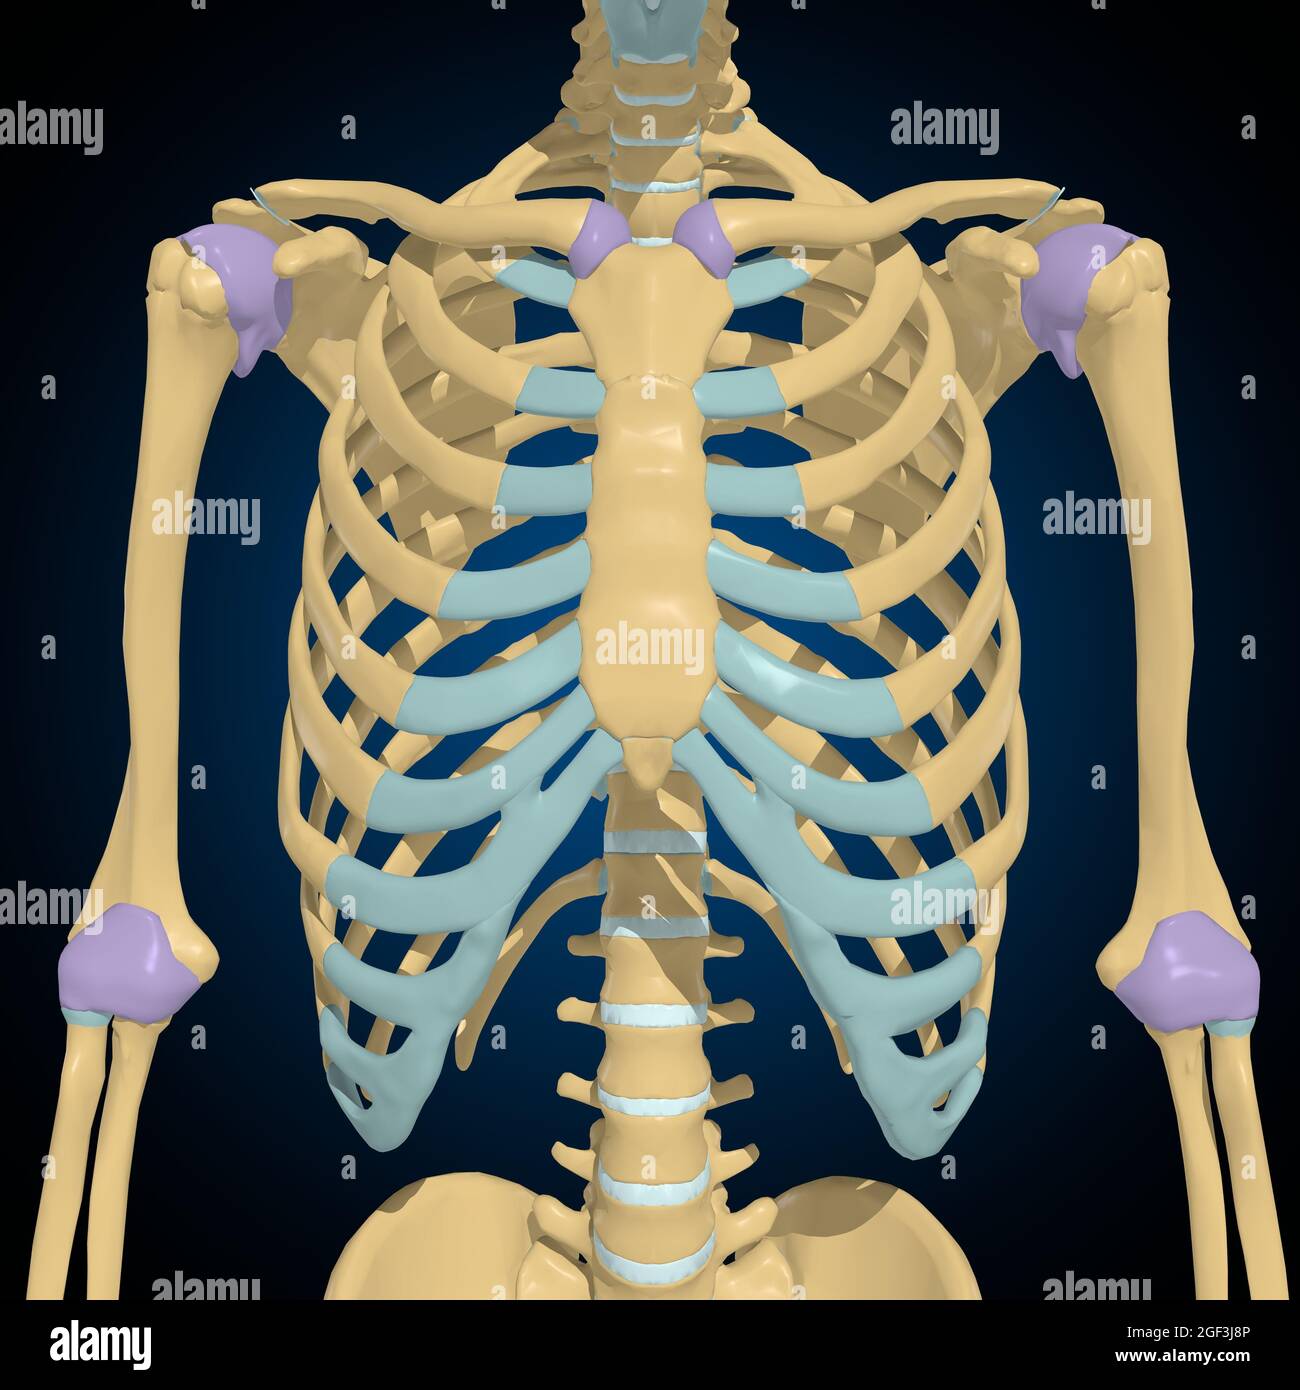

Articular capsule Anatomy For Medical Concept 3D Illustration Stock Photohttps://www.alamy.com/image-license-details/?v=1https://www.alamy.com/articular-capsule-anatomy-for-medical-concept-3d-illustration-image439559253.html

Articular capsule Anatomy For Medical Concept 3D Illustration Stock Photohttps://www.alamy.com/image-license-details/?v=1https://www.alamy.com/articular-capsule-anatomy-for-medical-concept-3d-illustration-image439559253.htmlRF2GF3J8N–Articular capsule Anatomy For Medical Concept 3D Illustration

Articular capsule Anatomy For Medical Concept 3D Illustration Stock Photohttps://www.alamy.com/image-license-details/?v=1https://www.alamy.com/articular-capsule-anatomy-for-medical-concept-3d-illustration-image439559233.html

Articular capsule Anatomy For Medical Concept 3D Illustration Stock Photohttps://www.alamy.com/image-license-details/?v=1https://www.alamy.com/articular-capsule-anatomy-for-medical-concept-3d-illustration-image439559233.htmlRF2GF3J81–Articular capsule Anatomy For Medical Concept 3D Illustration

Articular capsule Anatomy For Medical Concept 3D Illustration Stock Photohttps://www.alamy.com/image-license-details/?v=1https://www.alamy.com/articular-capsule-anatomy-for-medical-concept-3d-illustration-image439559176.html

Articular capsule Anatomy For Medical Concept 3D Illustration Stock Photohttps://www.alamy.com/image-license-details/?v=1https://www.alamy.com/articular-capsule-anatomy-for-medical-concept-3d-illustration-image439559176.htmlRF2GF3J60–Articular capsule Anatomy For Medical Concept 3D Illustration

Articular capsule Anatomy For Medical Concept 3D Illustration Stock Photohttps://www.alamy.com/image-license-details/?v=1https://www.alamy.com/articular-capsule-anatomy-for-medical-concept-3d-illustration-image439559162.html

Articular capsule Anatomy For Medical Concept 3D Illustration Stock Photohttps://www.alamy.com/image-license-details/?v=1https://www.alamy.com/articular-capsule-anatomy-for-medical-concept-3d-illustration-image439559162.htmlRF2GF3J5E–Articular capsule Anatomy For Medical Concept 3D Illustration

Articular capsule Anatomy For Medical Concept 3D Illustration Stock Photohttps://www.alamy.com/image-license-details/?v=1https://www.alamy.com/articular-capsule-anatomy-for-medical-concept-3d-illustration-image439559178.html

Articular capsule Anatomy For Medical Concept 3D Illustration Stock Photohttps://www.alamy.com/image-license-details/?v=1https://www.alamy.com/articular-capsule-anatomy-for-medical-concept-3d-illustration-image439559178.htmlRF2GF3J62–Articular capsule Anatomy For Medical Concept 3D Illustration

Articular capsule Anatomy For Medical Concept 3D Illustration Stock Photohttps://www.alamy.com/image-license-details/?v=1https://www.alamy.com/articular-capsule-anatomy-for-medical-concept-3d-illustration-image439559254.html

Articular capsule Anatomy For Medical Concept 3D Illustration Stock Photohttps://www.alamy.com/image-license-details/?v=1https://www.alamy.com/articular-capsule-anatomy-for-medical-concept-3d-illustration-image439559254.htmlRF2GF3J8P–Articular capsule Anatomy For Medical Concept 3D Illustration